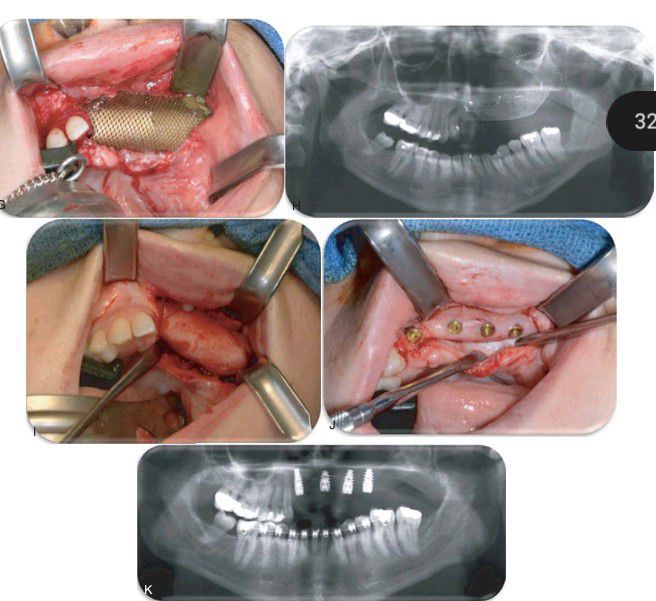

d (G) The “titanium crib” is secured to the native ridge with 1.2-mm self-drilling screws. (H) Panorex image after the grafting procedure. Titanium crib and graft reestablishing normal alveolar ridge height. (I) View of the regenerated ridge at surgical reentry 9 months after grafting. (J) Placement of four dental implants into the regenerated ridge. (K) Panorex after implant placement. (L) Tissue healing under a temporary fixed prosthesis. (M) Screw retained zirconia hybrid framework with pink porcelain to replace gingival tissues.